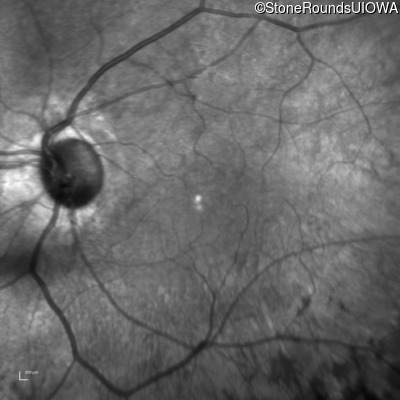

Infrared Fundus Photograph - Left - 20/25

Exemplar